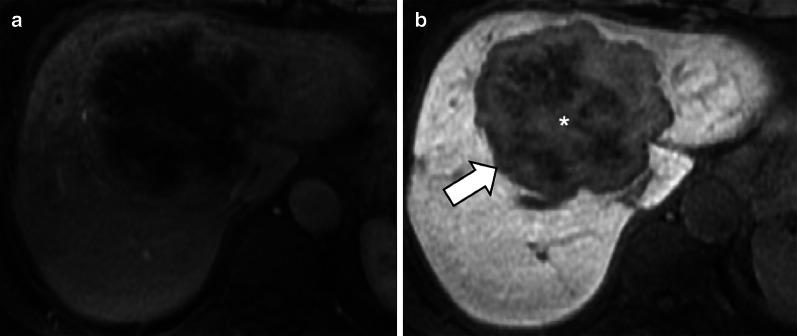

Hepatobiliary MRI contrast agents are increasingly being used for liver imaging. In clinical practice, most focal liver lesions do not uptake hepatobiliary contrast agents. Less commonly, hepatic lesions may show variable signal characteristics on hepatobiliary phase. This pictorial essay reviews a broad spectrum of benign and malignant focal hepatic observations that may show hyperintensity on hepatobiliary phase in various clinical settings. In non-cirrhotic patients, focal hepatic observations that show hyperintensity in the hepatobiliary phase are usually benign and typically include focal nodular hyperplasia. In patients with primary or secondary vascular disorders, focal nodular hyperplasia-like lesions arise as a local hyperplastic response to vascular alterations and tend to be iso- or hyperintense in the hepatobiliary phase. In oncologic patients, metastases and cholangiocarcinoma are hypointense lesions in the hepatobiliary phase; however, occasionally they may show a diffuse, central and inhomogeneous hepatobiliary paradoxical uptake with peripheral rim hypointensity. Post-chemotherapy focal nodular hyperplasia-like lesions may be tricky, and their typical hyperintense rim in the hepatobiliary phase is very helpful for the differential diagnosis with metastases. In cirrhotic patients, hepatocellular carcinoma may occasionally appear hyperintense on hepatobiliary phase.

肝胆磁共振成像造影剂越来越多地用于肝脏成像。在临床实践中,大多数肝脏局灶性病变不摄取肝胆造影剂。较少见的是,肝脏病变在肝胆期可能表现出不同的信号特征。这篇图文并茂的文章回顾了一系列广泛的良性和恶性肝脏局灶性表现,这些表现在各种临床情况下的肝胆期可能呈高信号。在非肝硬化患者中,在肝胆期呈高信号的肝脏局灶性表现通常是良性的,典型的包括局灶性结节性增生。在原发性或继发性血管疾病患者中,局灶性结节性增生样病变是对血管改变的局部增生反应,在肝胆期往往呈等信号或高信号。在肿瘤患者中,转移瘤和胆管癌在肝胆期是低信号病变;然而,偶尔它们可能表现出弥漫性、中央性和不均匀的肝胆矛盾性摄取,周边呈低信号。化疗后局灶性结节性增生样病变可能较难鉴别,其在肝胆期典型的高信号边缘对与转移瘤的鉴别诊断非常有帮助。在肝硬化患者中,肝细胞癌在肝胆期偶尔可能呈高信号。